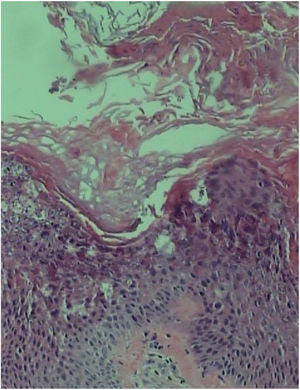

A biópsia de placa na porção extensora do antebraço mostrou acantose, papilomatose e hiperceratose com marcada epidermólise na camada granular (fig. 4).

Na histopatologia, as lesões hiperceratóticas da IEA revelam hiperqueratose, acantose e camada granular espessada. Os queratinócitos nas camadas espinhosas e granulosas superiores da epiderme podem apresentar vacuolização citoplasmática e grânulos de cerato‐hialina proeminentes.1,2,4,6 Os queratinócitos basais parecem normais, mas o número de mitoses está aumentado. Como achados da microscopia eletrônica, foram descritos filamentos anormais de queratina nos queratinócitos suprabasais, células da camada granular com grânulos aumentados de querato‐hialina e acúmulo de tonofilamentos, mostraram‐se espessados com disposição perinuclear em forma de anel interrompido.4,5